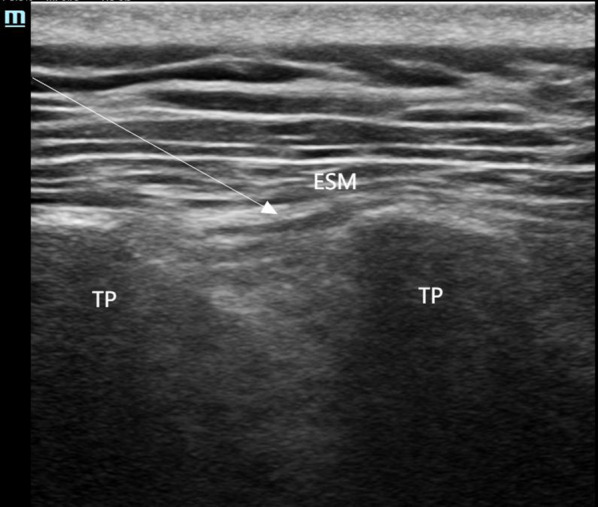

Introduction: Breast cancer surgery is a common surgical procedure often associated with acute and chronic postoperative pain. As part of multimodal analgesia, the erector spinae plane block (ESPB) has been shown to effectively alleviate pain after breast cancer surgery. This study is the first to apply the posterior quadratus lumborum block (posterior QLB) for perioperative analgesia in breast cancer surgery. The aim of this research was to evaluate whether ESPB and QLB2 can relieve acute and chronic pain following breast cancer surgery.

Methods: A total of 120 female patients undergoing breast cancer surgery were randomly assigned to receive either ESPB, posterior QLB, or no intervention. All patients were administered sufentanil patient-controlled intravenous analgesia postoperatively. The primary outcome was the visual analog scale (VAS) pain scores recorded at 2, 6, 18, 24, and 48 h post-surgery under rest and motion conditions. Secondary outcomes included the incidence of moderate-to-severe pain within 24 and 48 h post-surgery, intraoperative fentanyl cumulative dosage, postoperative rescue analgesia, chronic pain incidence, recovery quality of life, and adverse events.

Conclusion: Compared with conventional intravenous analgesia, the combination of ultrasound-guided ESPB and posterior QLB significantly reduces the incidence of moderate-to-severe pain and the need for rescue analgesia within 24 h post-surgery. Furthermore, a single posterior QLB significantly reduces the incidence of chronic pain at 3 months post-surgery in patients with breast cancer.